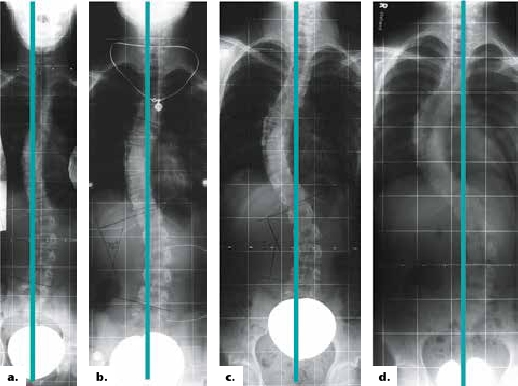

Alle erfolgreichen modernen Weiterentwicklungen der Derotationsorthesen wie z. B. die Korsette nach Rigo System Chêneau (RSC) oder Chêneau light streben eine Spiegelung des Krümmungsmusters und eine Überkorrektur an. Wenn diese Spiegelung nicht erreicht wird, kommt es zu keiner suffizienten Besserung der Skoliose (Abb. 2). Durch Spiegelungskorsette kommt es nicht zur exakten Spiegelung des Cobb-Winkels, sondern nur zu einer Verringerung desselben (Abb. 3). Wichtig erscheint aber nicht nur die Spiegelung, sondern auch die Schaffung ausreichender Freiräume, in die hinein geatmet werden kann und die somit für eine aktive Korrektur sorgen. Insbesondere dorsal ist ein entsprechender Raum wichtig (Abb. 4).

Für die meist jungen Patientinnen steht nicht der gemessene Cobb-Winkel im Vordergrund. Zwar ist dies ein Parameter, an dem sich der Therapieerfolg messen lässt, dennoch erscheinen Symmetrie und kosmetische Aspekte für die Patientinnen wesentlich wichtiger. Das behandelnde Team, bestehend aus Orthopäden, Orthopädie-Technikern und Physiotherapeuten, muss sich also auch hieran messen lassen. Ein kosmetisch gutes Ergebnis (siehe Abb. 3a, b u. 5a, b) entschädigt für eine jahrelange Versorgung mit einem Korsett, die zu einer deutlichen Minderung der Lebensqualität führt 10. Gut derotierende Rumpf-Korsette haben auf eine mehr oder minder weiche Wirbelsäulen-Verkrümmung der noch wachsenden Jugendlichen einen passiven oder aktiven Korrektur-Effekt. Es stellt sich jedoch die Frage, ob neben der meist guten passiven Korrektur in einem modernen derotierenden Rumpf-Korsett auch eine entsprechende aktive Aufrichtung durch die Jugendlichen möglich ist.